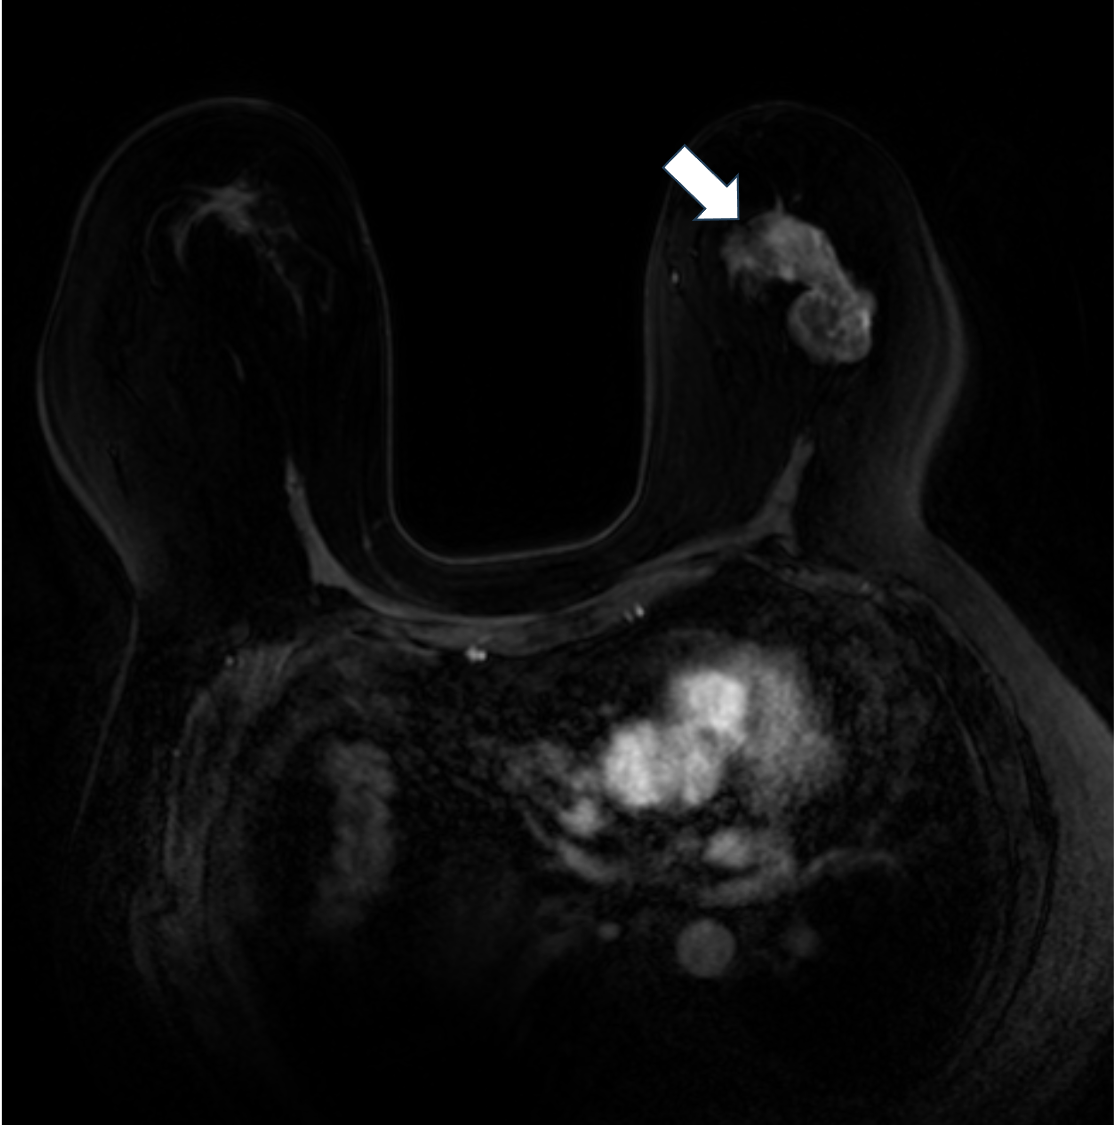

3. 拡散強調画像 b=1000(s/mm2)(造影前)

拡散強調像では腫瘤の乳頭側が高信号を示すが、それ以外の部分は周囲の乳腺組織と同等の信号を示す。乳頭側に細胞密度の高い腫瘍の存在が示唆される。